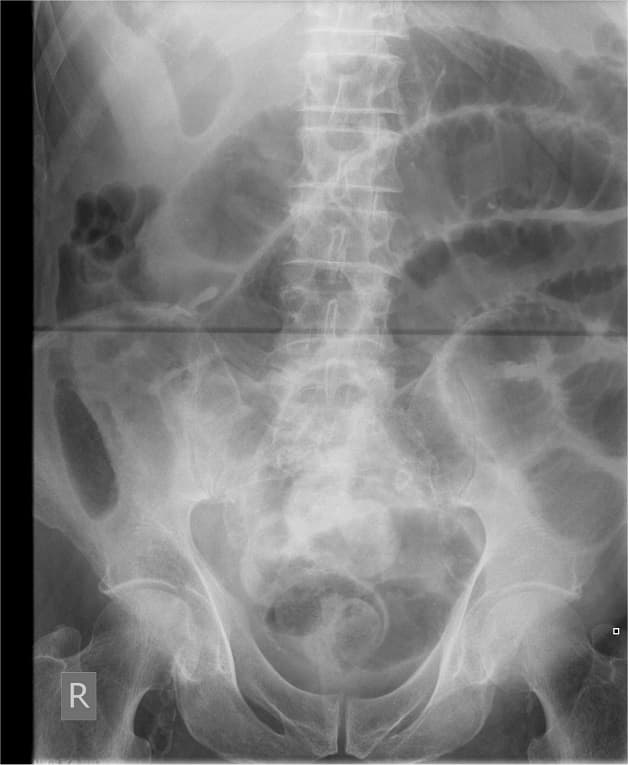

– Chụp X- quang, chụp CT để xác định vị trí viêm ruột thừa

Chụp X-quang giúp xác định tình trạng bệnh